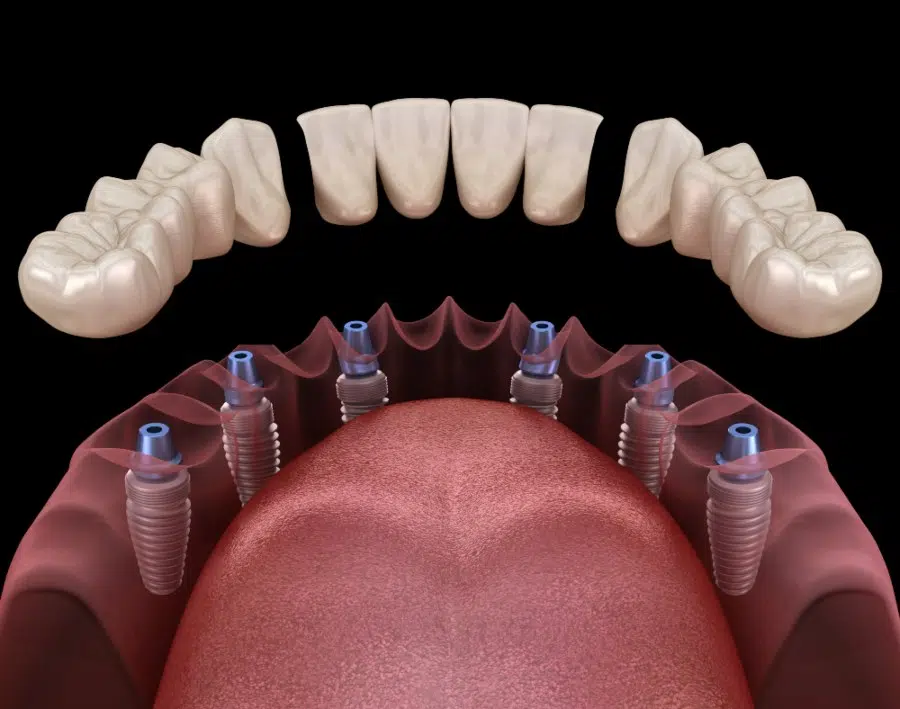

All on X implant systems include All on 4, All on 6 and All on 8 implant systems, which differ in how many screws are used per bridge. They are the best choice for patients who want to have the most affordable and very durable implant system for restoring many teeth at once. Patients who have more dense jaws and desire even better stability can choose All on 6 systems. More information about our All on X implant procedures, including All on 4 dental implants.

All on 4 implant systems have four screws per bridge and are among the most popular options at our clinic. Their cost is the lowest among all All on X systems.

All on 8 implant system are used when the greatest stability is required to support the fixed bridge.

3 on 6 implant system are a type of implant system which consists of three fixed bridges, each supported by two implant screws.